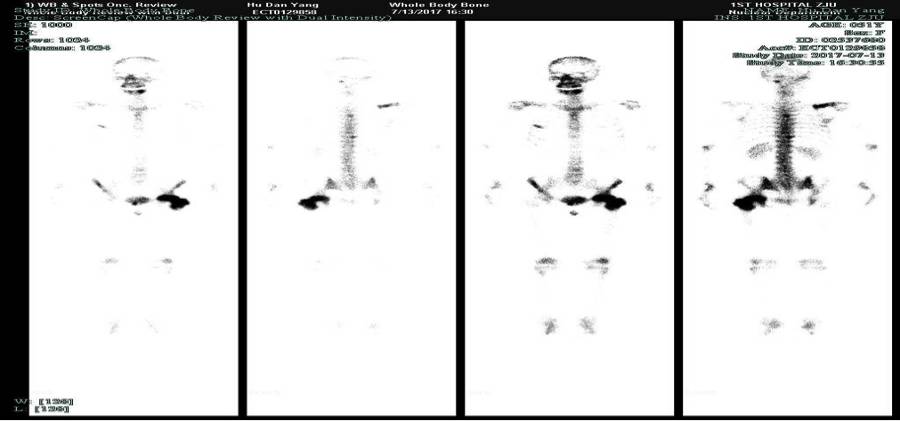

于是我院再次组织MDT讨论,选择戈舍瑞林+氟维司群作为内分泌维持治疗方案(经检查确认胡女士尚未绝经),并继续给予唑来膦酸。患者耐受性良好。2017年7月骨骼ECT复查提示部分骨病灶代谢较前有所降低。

至今胡女士已接受戈舍瑞林+氟维司群治疗8+月,未出现任何身体不适,疗效评价SD。

图四:2017.7.13骨骼ECT:骨骼(颈椎上段左缘、右侧肩胛骨、右侧1后肋及5前肋、胸5、10椎体、双侧耻骨及左侧股骨上段见示踪剂分布异常浓聚)骨质代谢活跃,对照本院2017-03-13ECT片,部分病灶代谢较前有所降低。